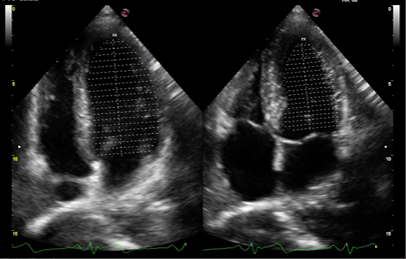

Xstrain – Comprehensive assessment for the myocardial strain of Left Ventricle, a useful tool to evaluate the LV function and Heart diseases

Auto EF – Automatic measurement of the EF fraction